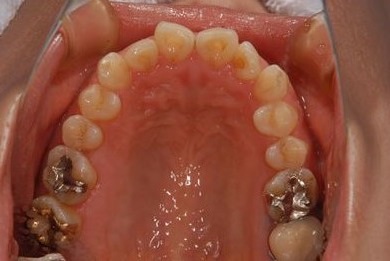

インプラント治療+セラミック治療+歯肉歯槽骨整形

| 性別/年齢 | 女性 / 38歳 | ||||||||||||||||||||||||||||||||

| 主訴 | 右下奥の欠損のため、インプラントを希望。また、左に物が挟まりやすいための治療も希望。 | ||||||||||||||||||||||||||||||||

| 治療内容 | インプラント1本、ジルコニアフレームオールセラミッククラウン2本(ジルコニアセラミック用土台1本)、歯肉歯槽骨整形 | ||||||||||||||||||||||||||||||||

| 総治療費 | 713,580円 | ||||||||||||||||||||||||||||||||

| 治療期間 | 10ヶ月 |